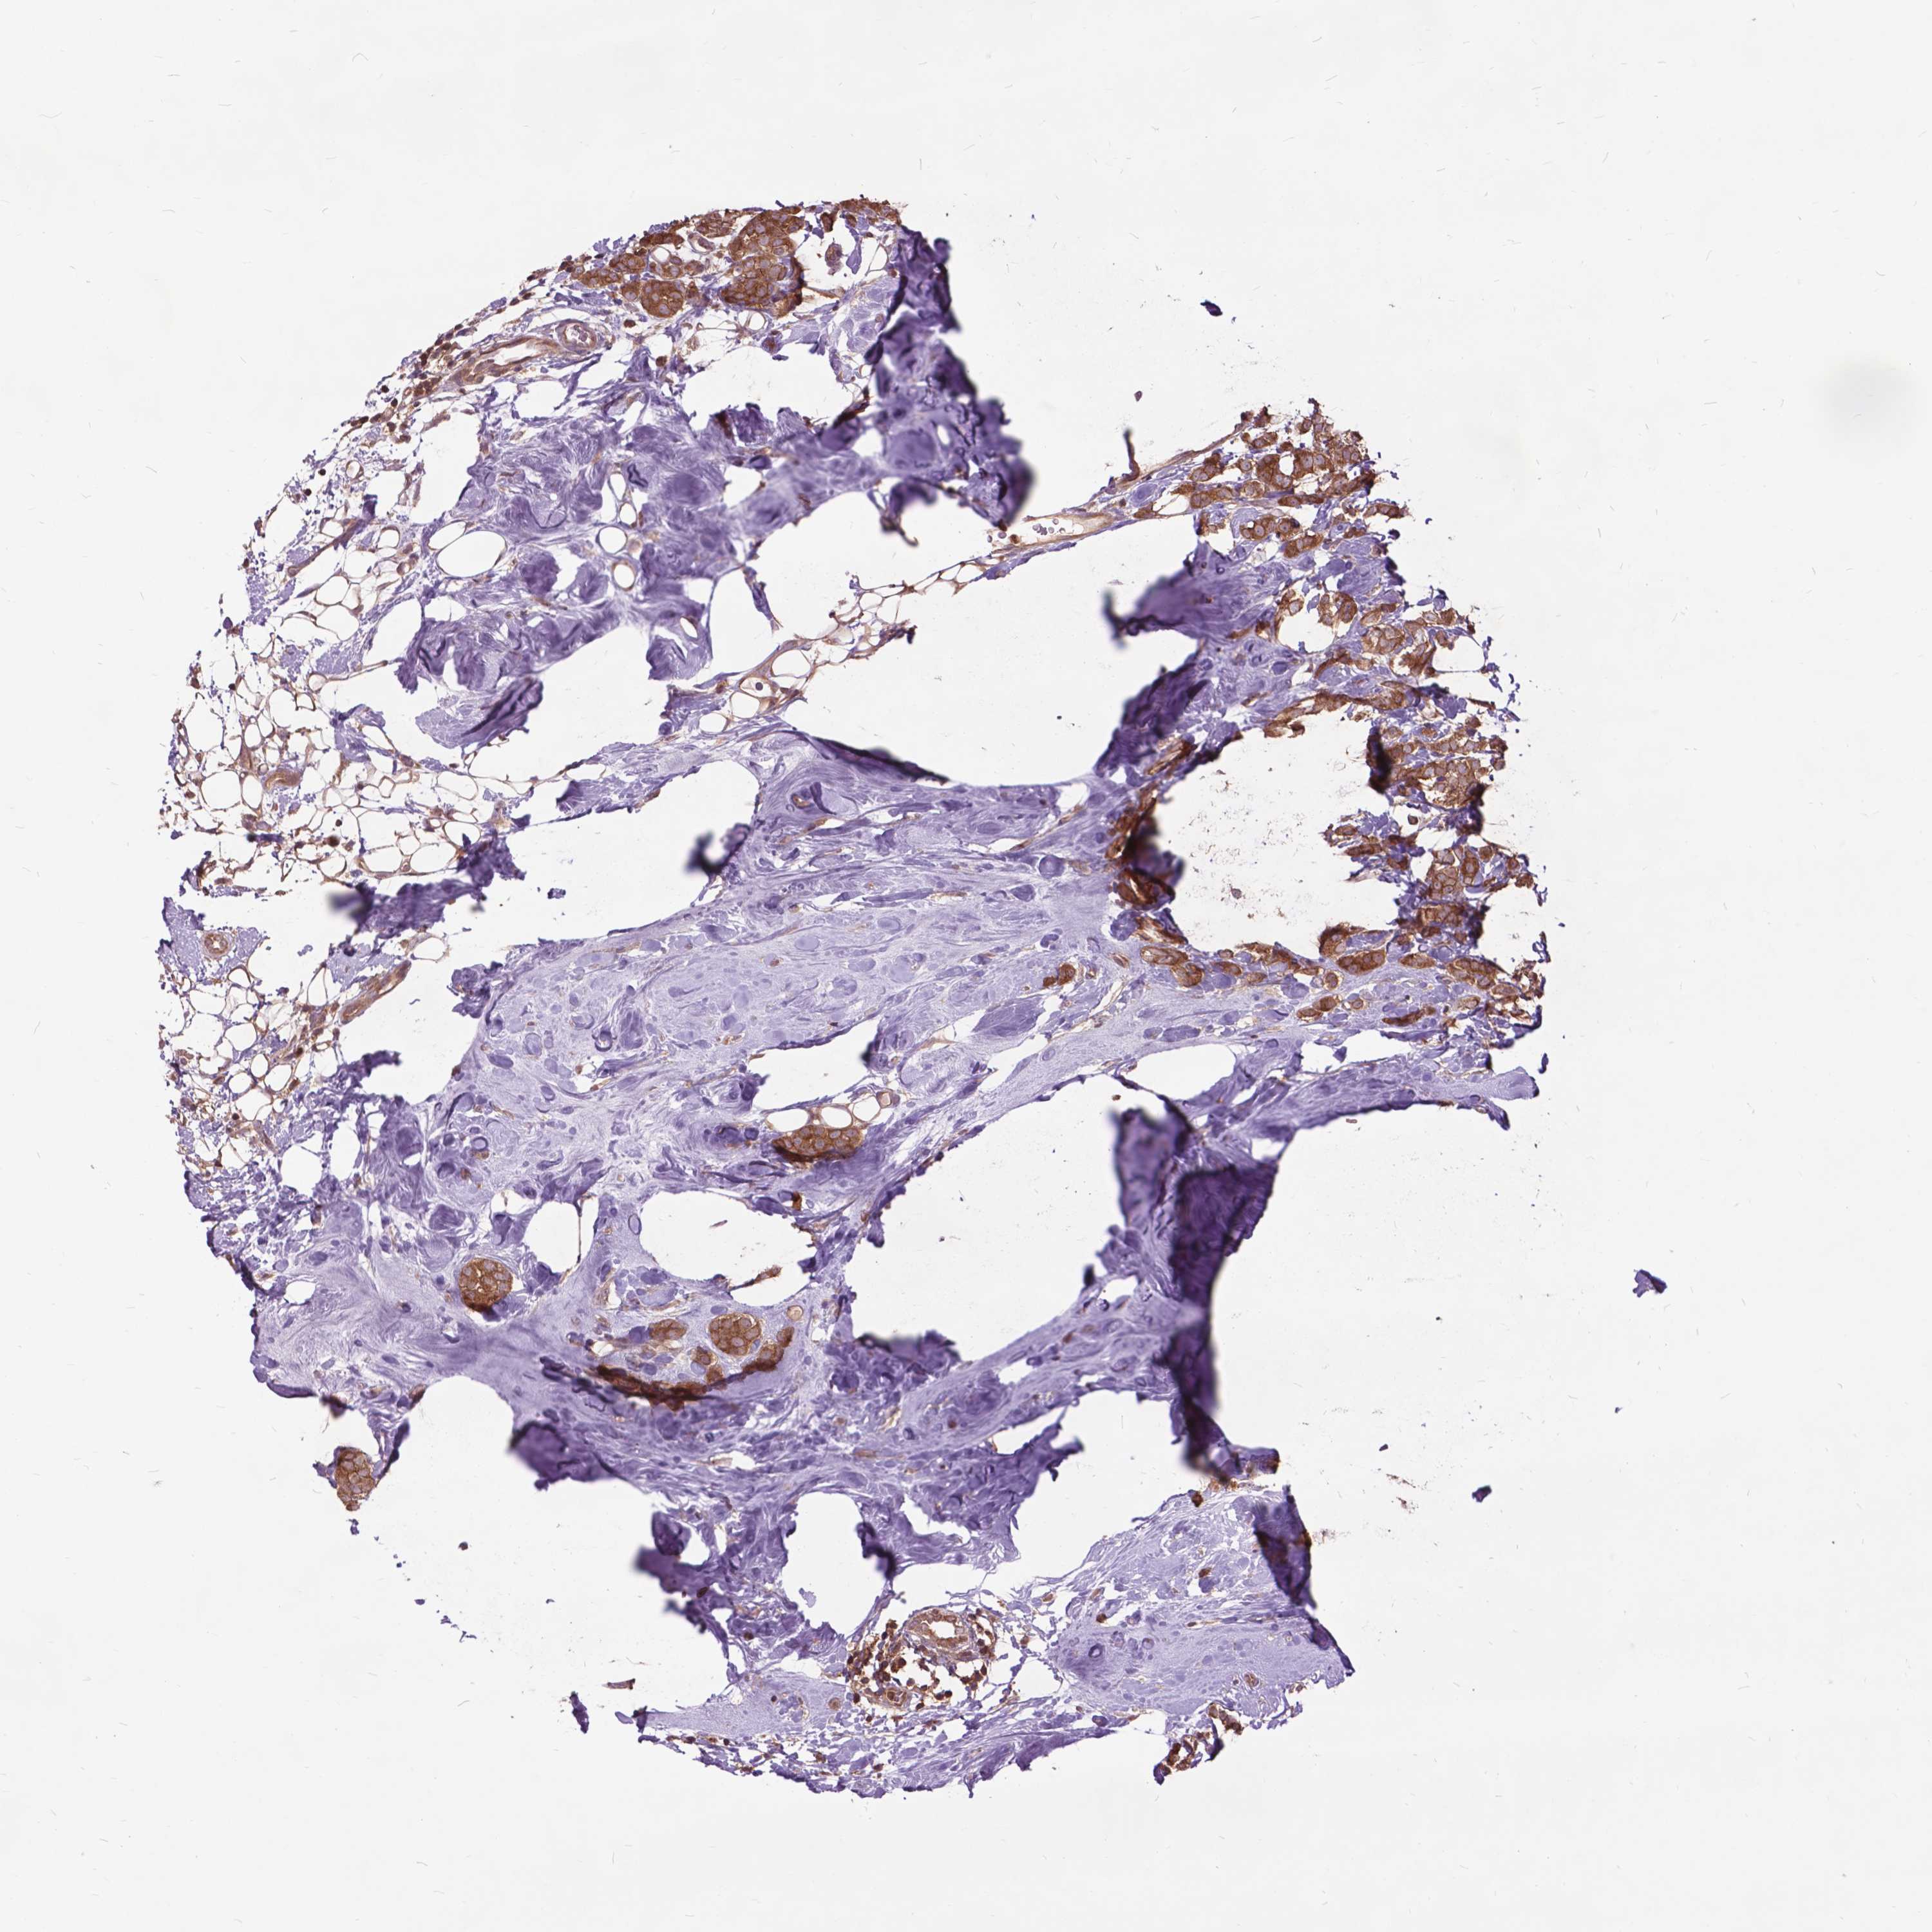

BRCA TCGA BRCA VALIDATION PROTEIN EXPRESSION

ANTIBODIES

AND

VALIDATION